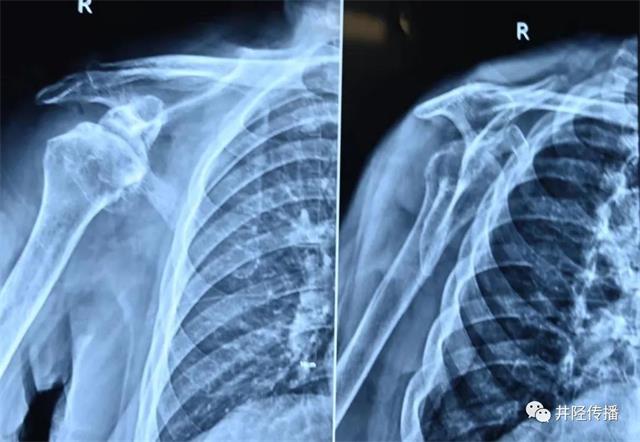

术前影像

今年86岁的张婆婆,右肩疼痛10余年,连抬肩、吃饭、洗漱等简单动作都难以完成,夜间疼痛更是剧烈,严重影响睡眠和生活质量。近日,在家人陪同下辗转来到井陉县医院关节外科就诊。

李计东书记、李博副书记带领关节外科团队完善一系列检查后,诊断为右侧巨大肩袖损伤(不可修复型)、右肩关节炎。在麻醉科、手术室医护人员配合下,为患者实施了反肩关节置换术,1小时后手术成功完成,使张婆婆右肩重获“新生”!